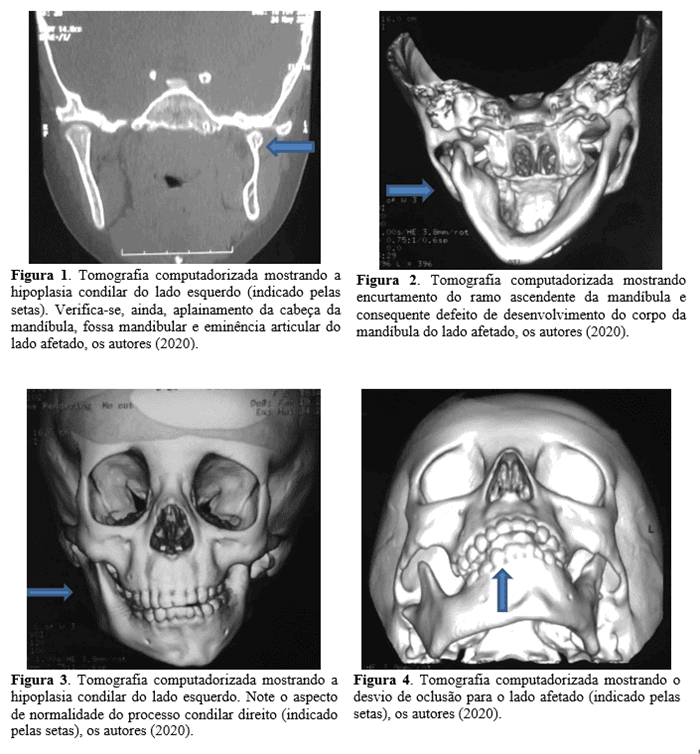

Первоначально было проведено дополнительное обследование полости рта, в ходе которого была обнаружена асимметрия лица в дополнение к отклонению в движении открывания рта. Чтобы лучше оценить костные структуры лица и ВНЧС, потребовалась компьютерная томография. КТ показала гипоплазию мыщелков с левой стороны, также можно было проверить, что поверхности суставных костей на этой стороне (возвышение сустава, мыщелковый отросток и нижнечелюстная ямка) уплощены, в дополнение к укорочению восходящей ветви нижней челюсти на стороне поражения и порок развития тела челюсти. Однако на правой стороне все компоненты суставной кости были в пределах нормы. (Рисунок 1) –

ПОЛУЧЕННЫЕ РЕЗУЛЬТАТЫ